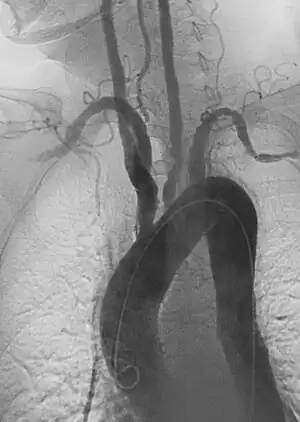

- Angiography: Sometimes referred to as traditional angiography, catheter angiography or digital subtraction angiography (DSA). A small needle is inserted into a blood vessel, then exchanged for a catheter over a wire. The catheter is directed at the vessel to be studied, and contrast is directly injected to evaluate the lumen under video X-ray. This is an older technique than modern CT angiography or MR angiography, but provides unique advantages. With a catheter in place, provocative maneuvers can be performed such as breath holds or instillation of vasodilators, to evaluate a patient's blood flow dynamically. This can reproduce symptoms and identify functional abnormalities in a vessel that a static CT or MR imaging cannot.[79][80] Angiography provides the basis for all endovascular therapy.

- Aortic aneurysms include thoracic, abdominal and thoracoabdominal aneurysms. Treatment strategies are customized depending on the location, size, rate of growth and extent of the aneurysm as well as the medical comorbidities of the patient. For example, an intact, small but slowly growing aneurysm may be safely monitored with serial imaging for months or years before elective repair is considered. Elective endovascular aortic grafting is now routinely attempted when possible. Endovascular aortic repair (EVAR) refers to treatment of an abdominal aortic aneurysm, while thoracic endovascular aortic repair (TEVAR) is performed on the thoracic aorta. A ruptured aneurysm may be taken emergently for open, endovascular or combination repair.